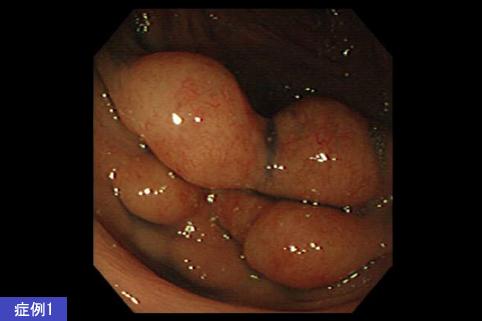

疾病(病理主体)的分类恶性淋巴系肿瘤/恶性淋巴瘤

部位(按器官分)大肠/升结肠

检查方法内窥镜

肿瘤最大直径25~29

肿瘤的深度sm